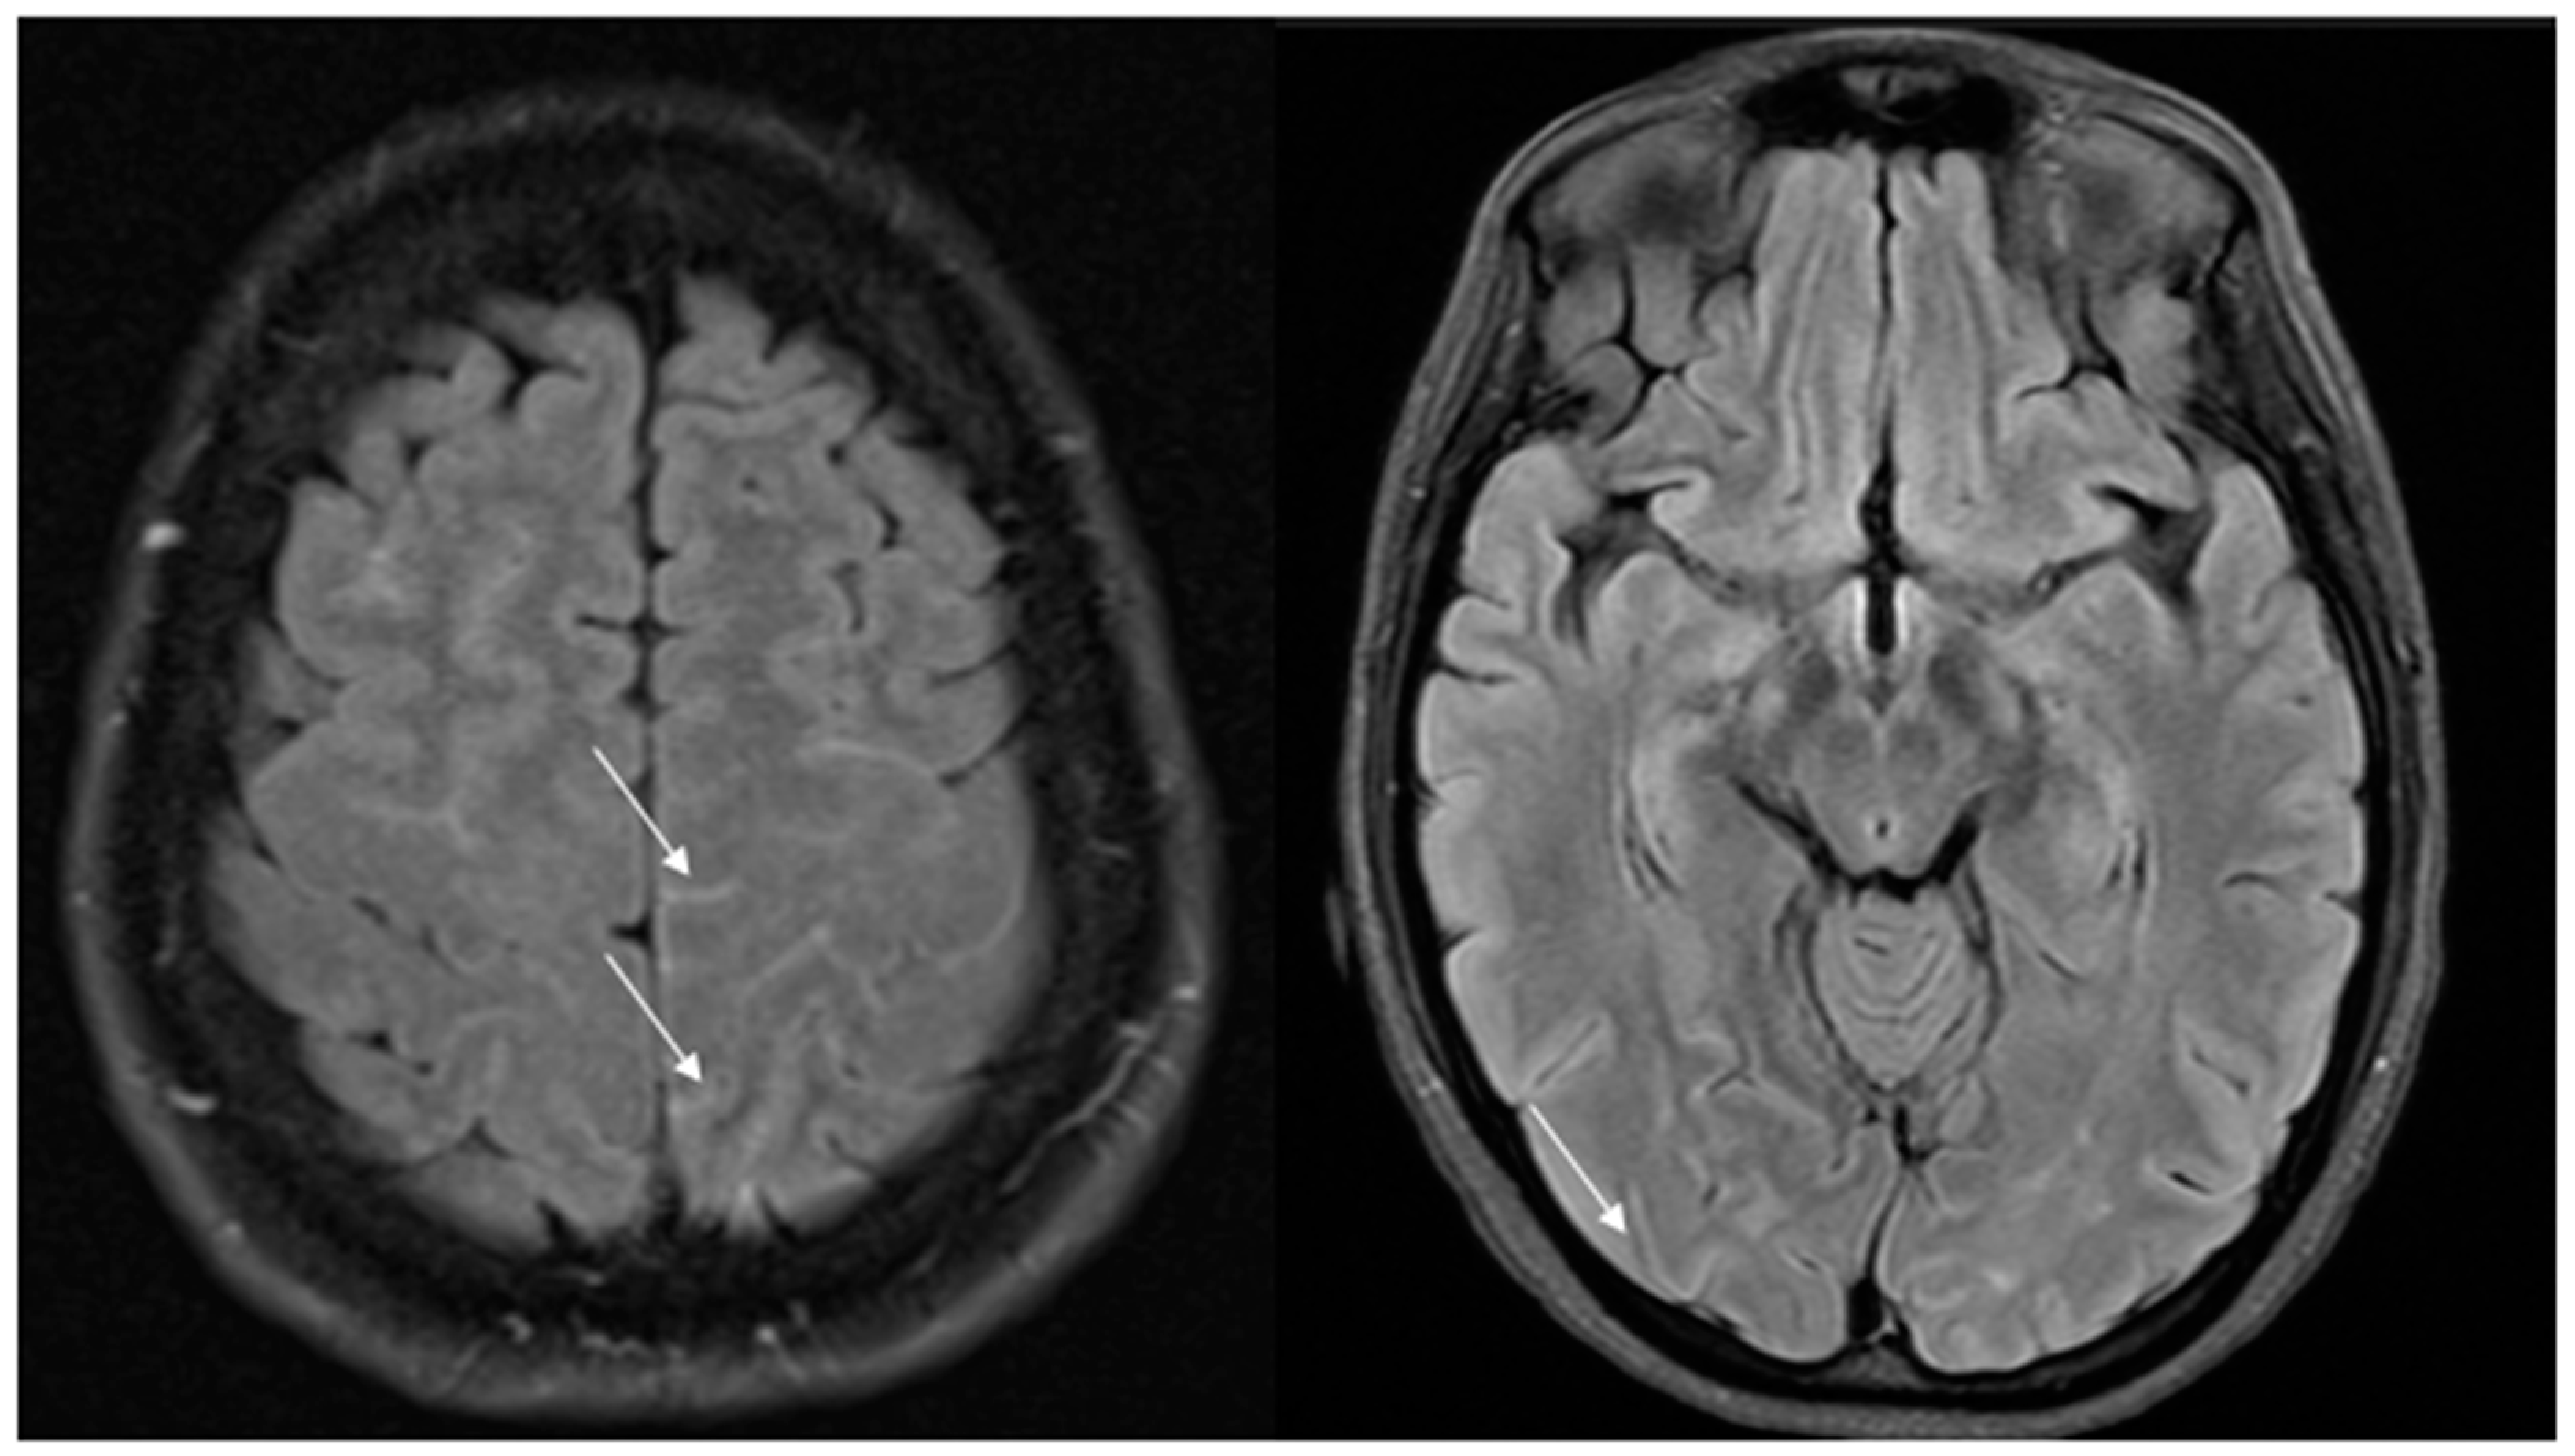

As previously said, vasospasm initially involves only small distal cerebral vessels not depicted by MRA and then centripetally spreads to larger vessels over days or weeks. As a consequence, initial brain MRI is normal in 30–55% of cases, while initial MRA is normal in 22% of cases [9]. Nevertheless, vascular FLAIR hyperintensities as early signs can be visible on T2/FLAIR sequences, even before vasospasm becomes visible on MRA [72]. Well-circumscribed dot or tubular-like appearances of hyperintense lesions running through the sulci, correlating with slow flow on the cortical surface, have been described. These hyperintense vessels (HVs) are often bilateral, involving the territories of the middle cerebral artery (MCA) and posterior cerebral artery (PCA) (Figure 2).

More frequently, HVs are observed in patients with PRES and ischemic stroke, suggesting that they may not only serve as a useful marker of RCVS but may also indicate clinical severity. HVs are distinct from subarachnoid hemorrhage, as they do not appear hypointense on SWI sequences [72]. Vasospasm, on the other hand, can be visualized with magnetic resonance angiography (MRA) or through computed tomography angiography (CTA) (as shown on Figure 3) when it starts involving larger cerebral vessels. As a result, the diagnosis could be challenging in the acute phase and often delayed. In cases of treatment-related RCVS, cerebral edema is more frequently observed and vasoconstriction is more widespread and severe compared to the idiopathic form where vasoconstriction is usually segmental.

Figure 2. Hyperintense vessels on FLAIR images in two patients with RCVS (arrows).